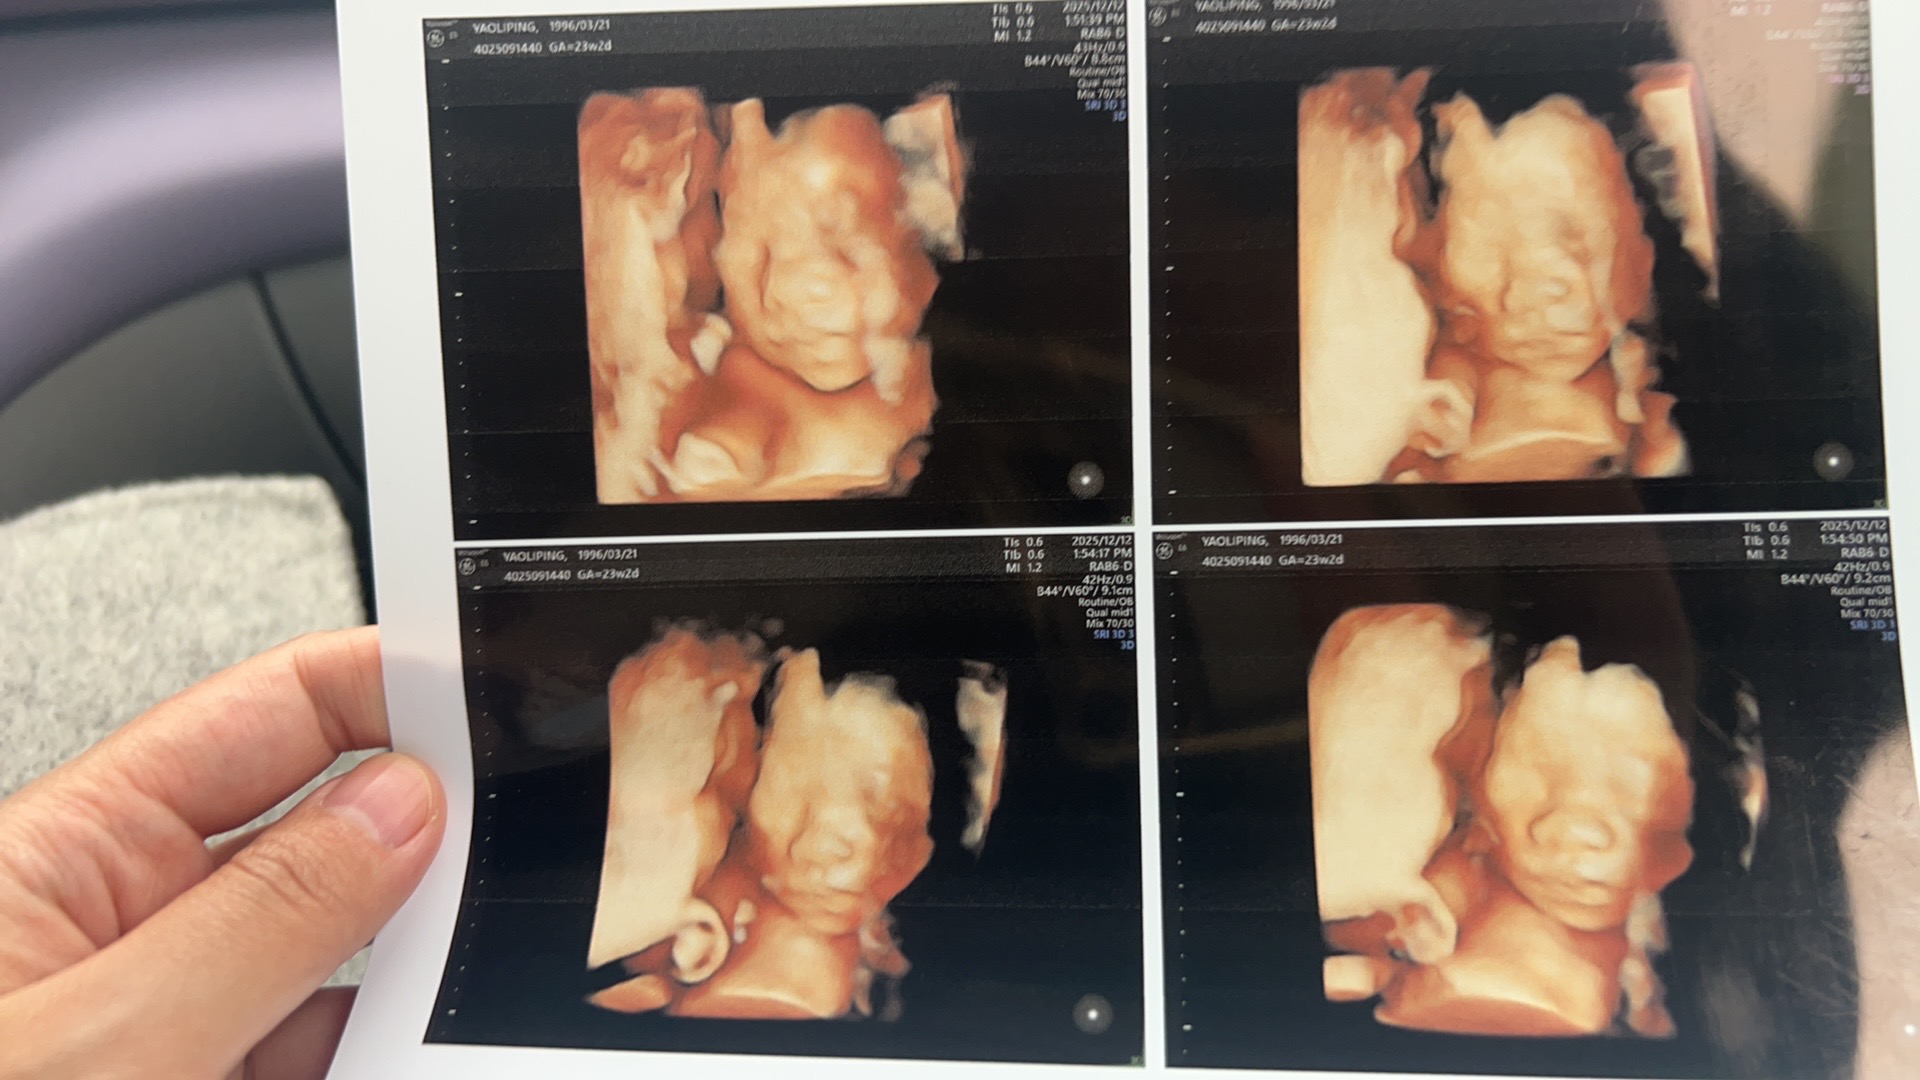

给大家看看我家小可爱的四维照片,虽然我觉得丑萌丑萌的,但婆婆说很可爱呢!